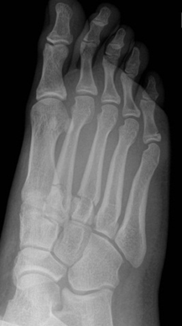

Single and multiple non-displaced metatarsal fractures

- Follow up Orthopaedic fracture clinic in 7 - 10 days.